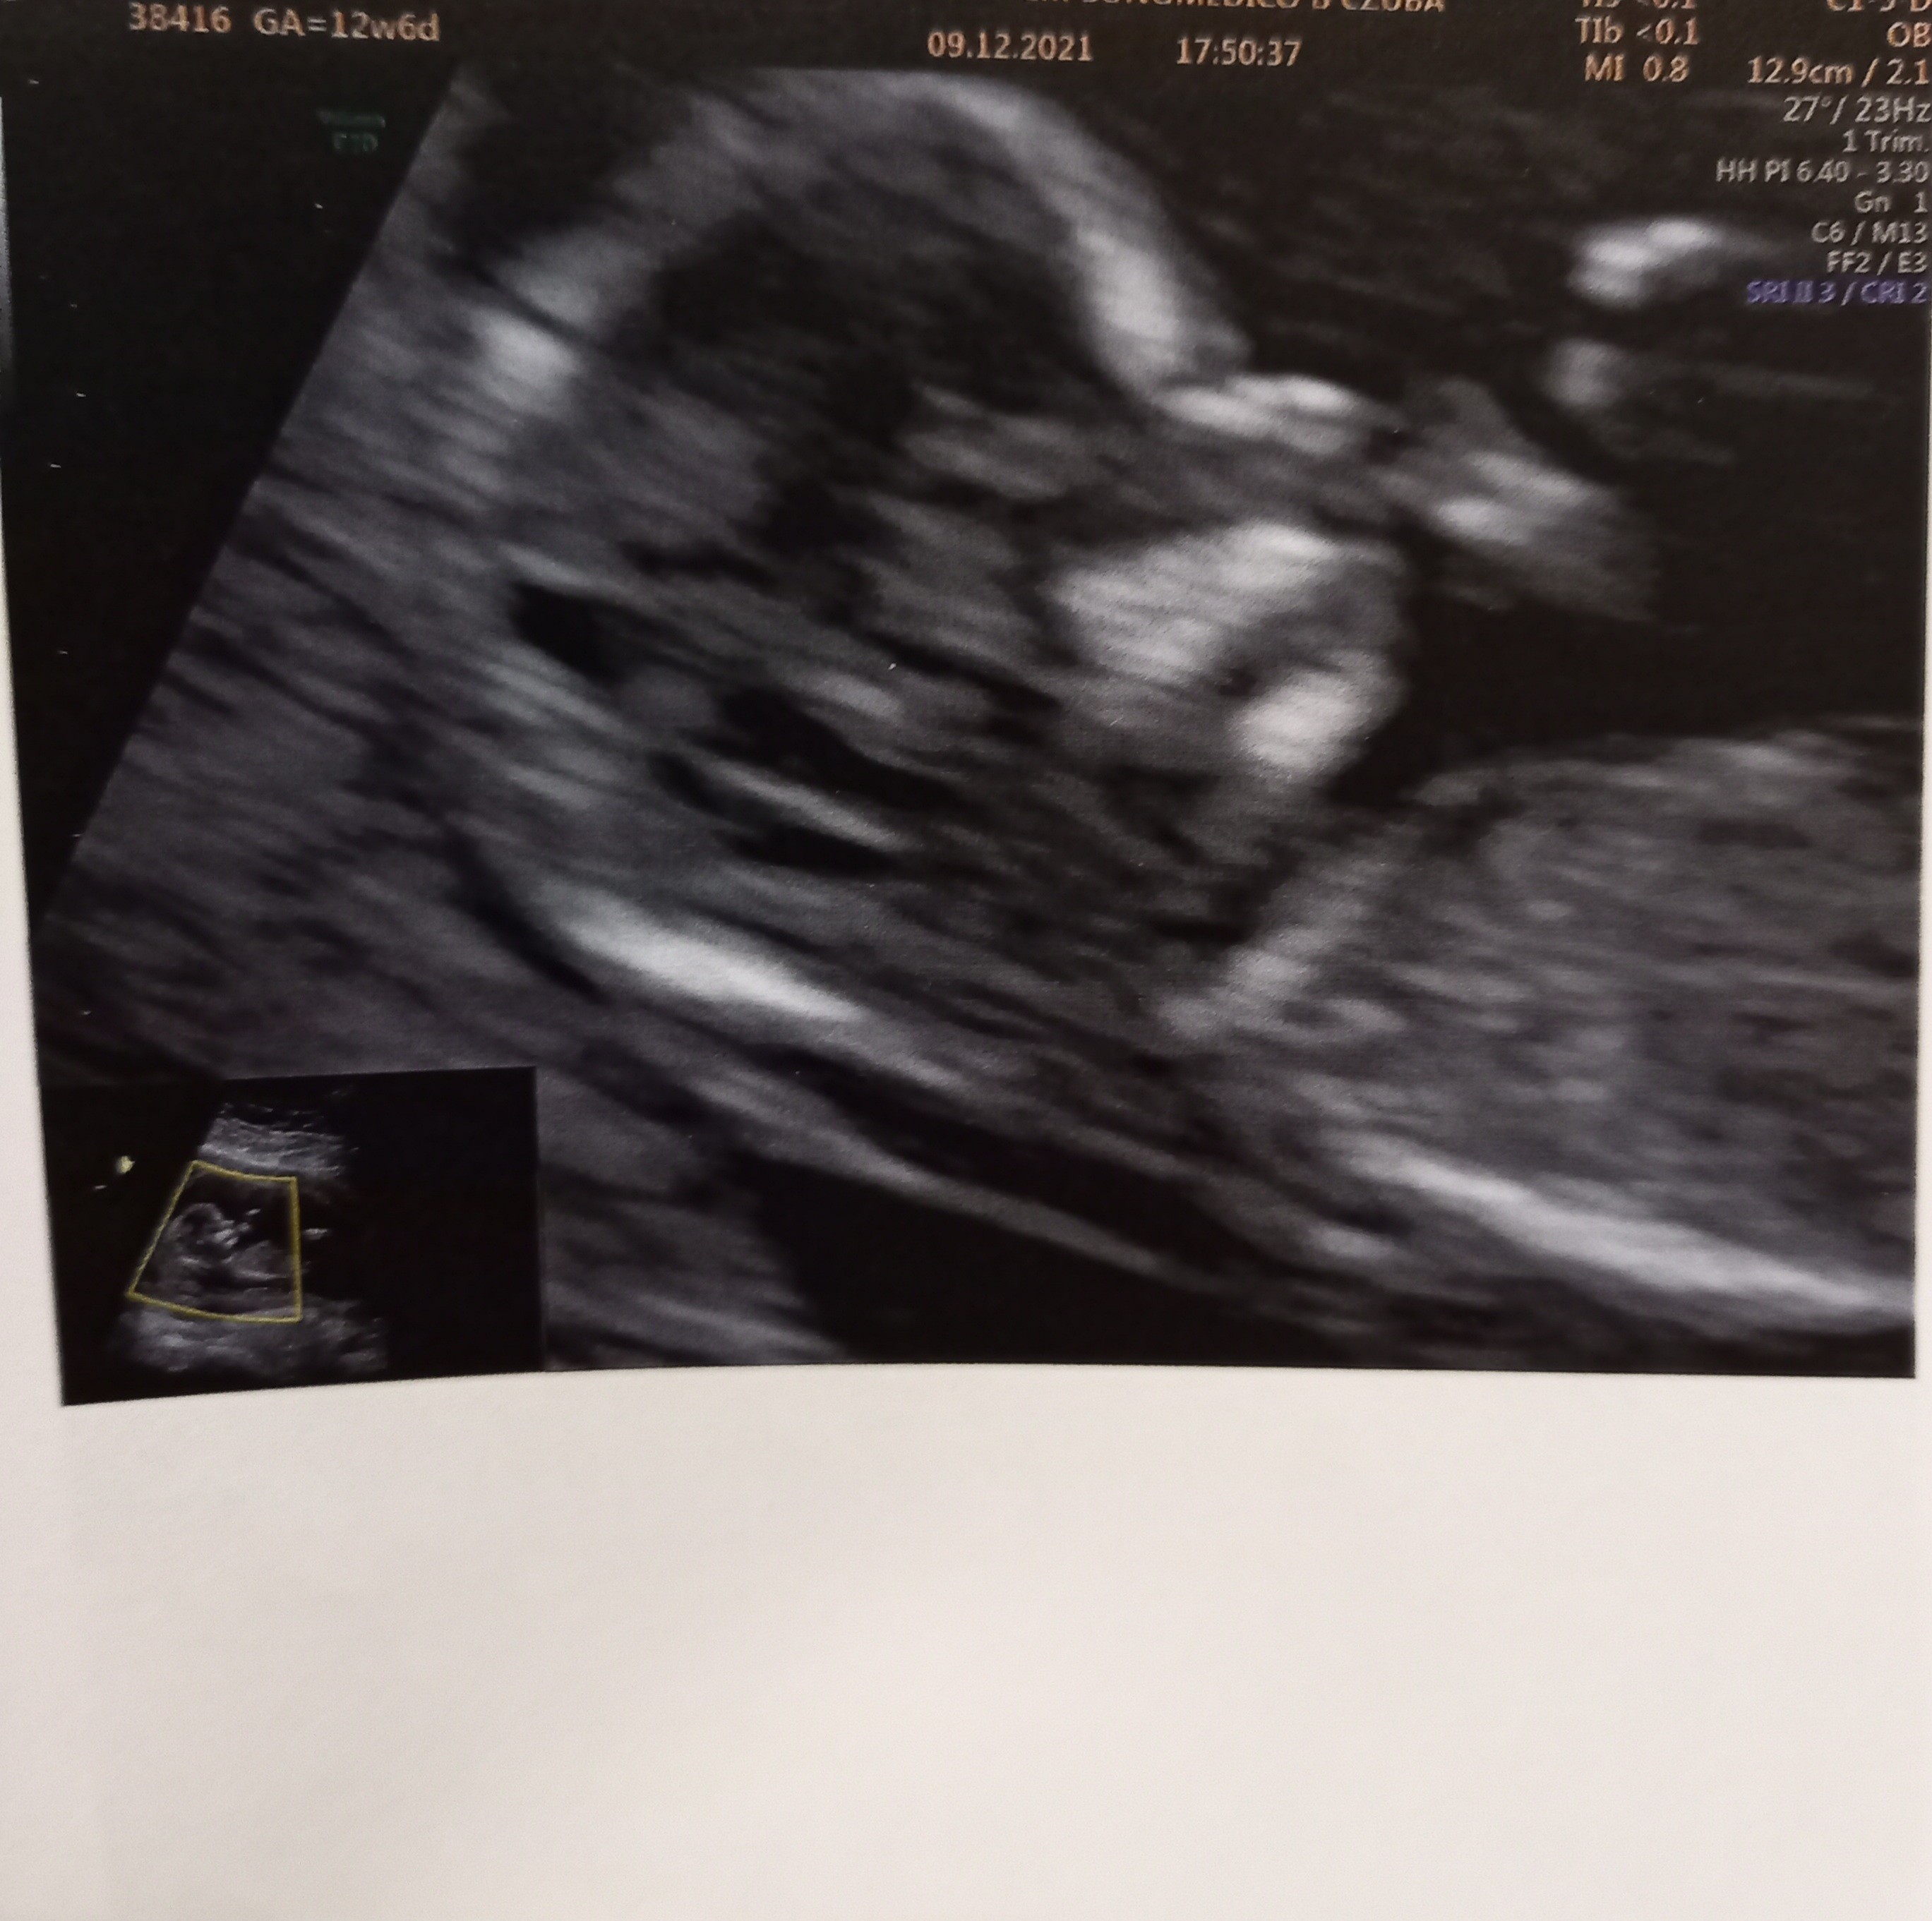

No i po badaniu... szczerze mówiąc to lekarz nic mi nie powiedział czy jest dobrze czy nie bo mam czekać na wyniki pappa i wtedy dostanę konkretne informacje... Z ciekawostek to z nifty dziewczynka a on mi mowi że 90% chłopiec... także hmmm komu bardziej ufać? Idę do swojego lekarza we wtorek to podpytam... nie mówiłam mu ze robiłam nifty bo nie chciałam nic sugerować ale aż jestem w szoku bo 90% to całkiem dużo